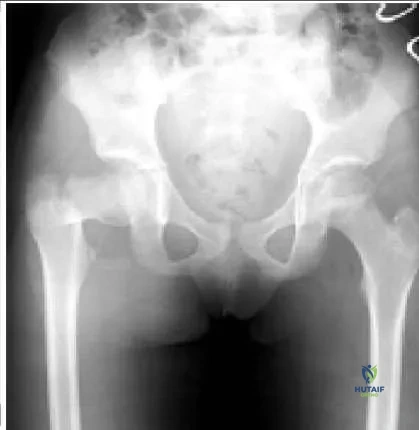

A 9-year-old girl sustains an injury (Slide 1) as a result of a fall. What is the recommended treatment:

This patient has a basicervical fracture, which is prone to development of varus. Traction, spica cast, and Steinman pin fixation do not provide adequate control of this process. Steinmann pins do not allow compression

across the fracture site. C losed or open reduction and internal fixation with a compression screw fixation, preferably a hip screw, provide the best control of the fracture. A hip screw provides the best protection against the development of varus. If the fracture is not opened, then aspiration of the hematoma is recommended.